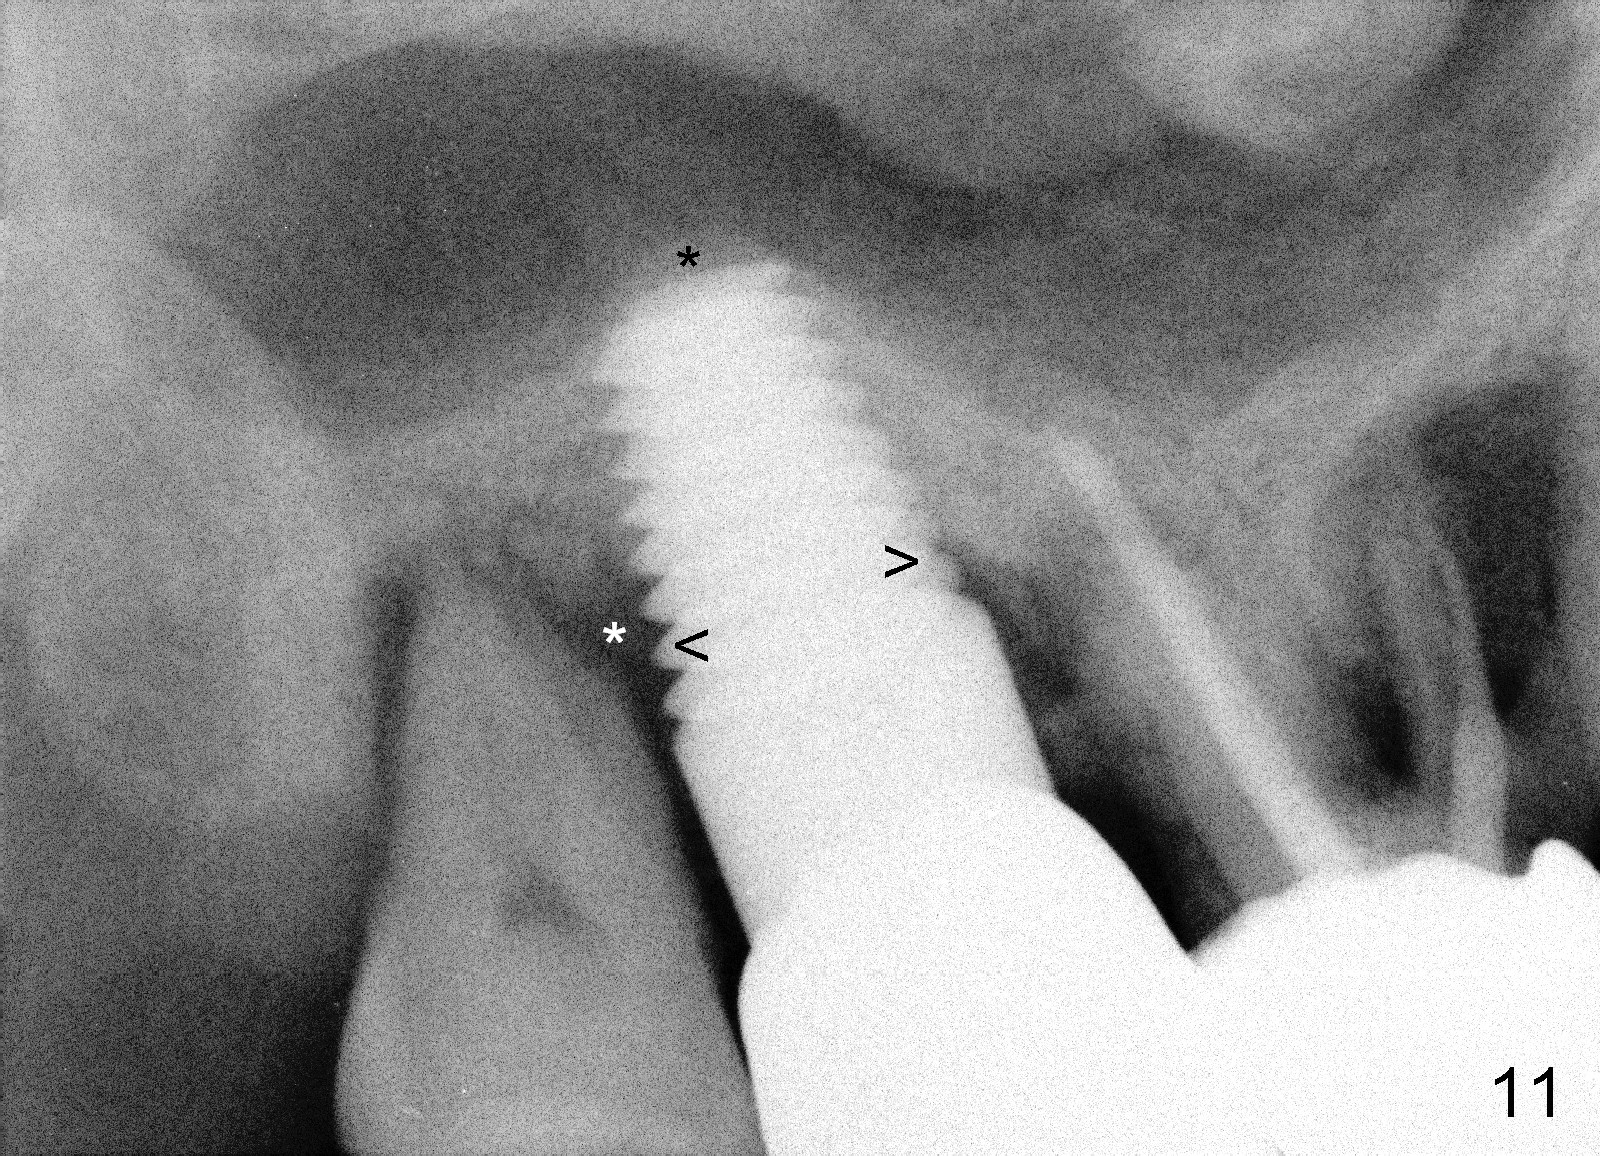

The patient complains food impaction between #1 and 2, six months post cementation. The former has mobility II. Although there is keratinized gingiva buccal to these sites (Fig.12), there is no papilla buccally (Fig.13) or palatally (Fig.14). The palatal pockets between #1 and 2 are deep with tenderness. X-ray shows bone loss between the sites (Fig.11 white *); the periodontal explorer can be felt to touch the distal implant threads (<). Extraction and immediate implant are recommended for #1. Twelve months later, the patient agrees with the treatment plan. The tooth #3 needs extraction and immediate implant, 2.5 years after the one at #2.